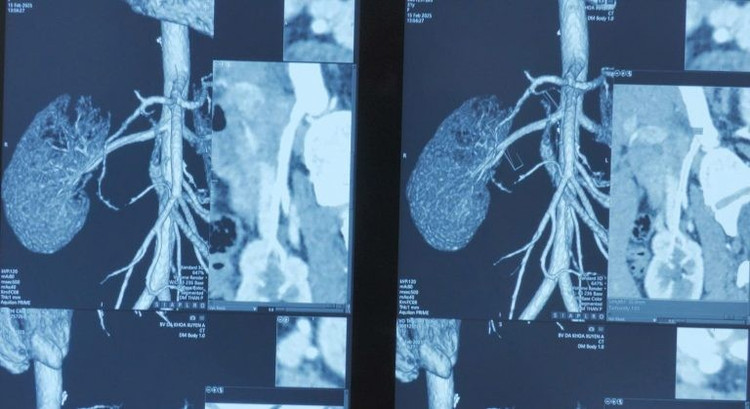

Hình ảnh MRI thận bệnh nhân suy thận mạn - Ảnh BVCC